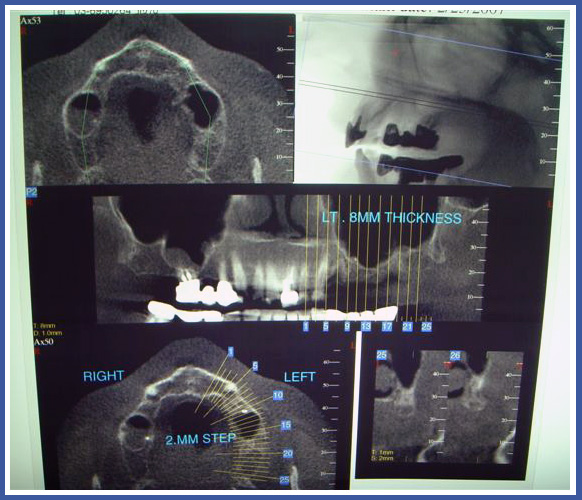

5. Компьютерная томография

Этот снимок выполняется в рентгеновском кабинете. Для выполнения этого снимка используется сочетание рентгеновских лучей и компьютерного сканирования, которое с помощью сложных расчетов может определить, какими тканями и каким образом будет поглощаться излучение.

В стоматологии обычно используют обычную компьютерную томографию, которая производит «срезы» челюстей и зубов и позволяет врачу видеть точную анатомию кости, зубов, максилярного синуса и канала нерва.

Обычно снимки компьютерной томографии (СТ) выполняются в дополнение к панорамным снимкам и перед имплантациями зубов для того, чтобы определить точное место, где будет установлен имплантант.

Эти снимки также помогают определить наличие воспалительных и опухолевых процессов.